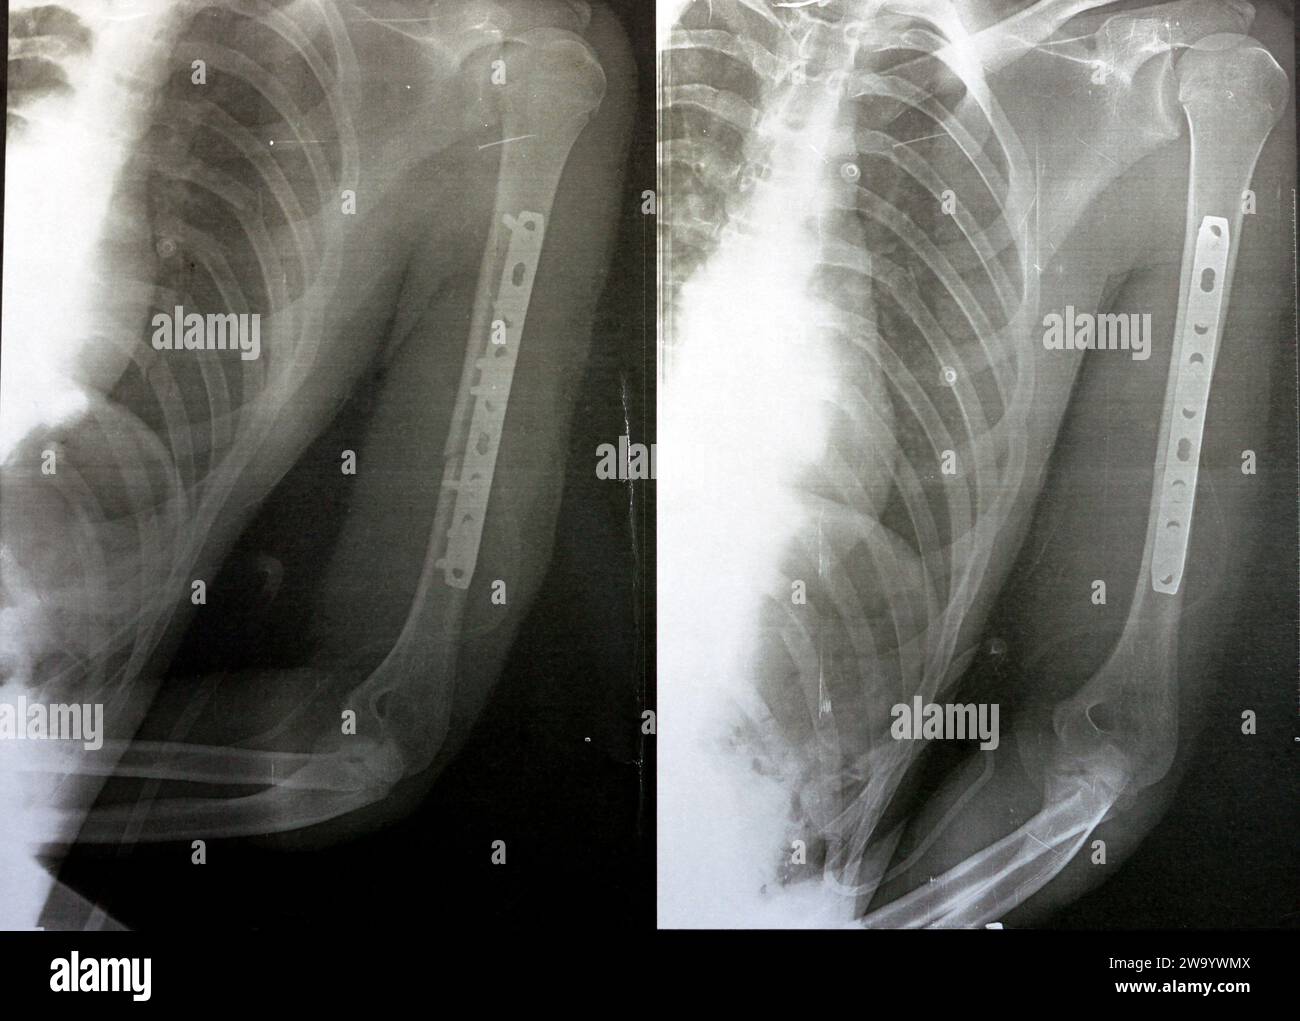

RF2WA30RC–Radiografia semplice che mostra frattura dell'omero sinistro dell'albero intermedio trasversale causata da un trauma diretto in un incidente stradale, gestito da riduzione aperta e fissa interna

RF2W9YW73–Radiografia semplice che mostra frattura dell'omero sinistro dell'albero intermedio trasversale causata da un trauma diretto in un incidente stradale, gestito da riduzione aperta e fissa interna

RF2WA2Y85–Radiografia semplice che mostra frattura dell'omero sinistro dell'albero intermedio trasversale causata da un trauma diretto in un incidente stradale, gestito da riduzione aperta e fissa interna

RF2W9YWMX–Radiografia semplice che mostra frattura dell'omero sinistro dell'albero intermedio trasversale causata da un trauma diretto in un incidente stradale, gestito da riduzione aperta e fissa interna

RF2W9YW6Y–Radiografia semplice che mostra frattura dell'omero sinistro dell'albero intermedio trasversale causata da un trauma diretto in un incidente stradale, gestito da riduzione aperta e fissa interna

RF2W9YWN6–Radiografia semplice che mostra frattura dell'omero sinistro dell'albero intermedio trasversale causata da un trauma diretto in un incidente stradale, gestito da riduzione aperta e fissa interna